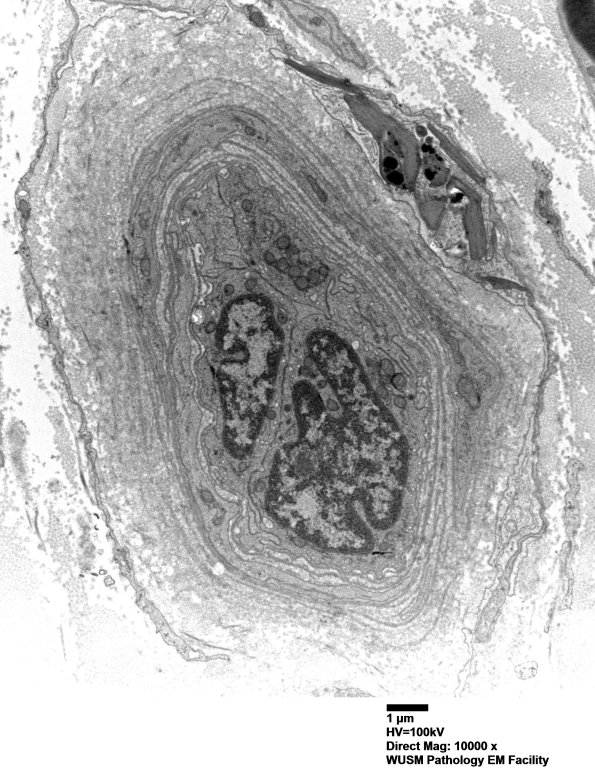

16B5,6 Accumulated intact basal membranes expand the vessel wall. (electron micrographs)